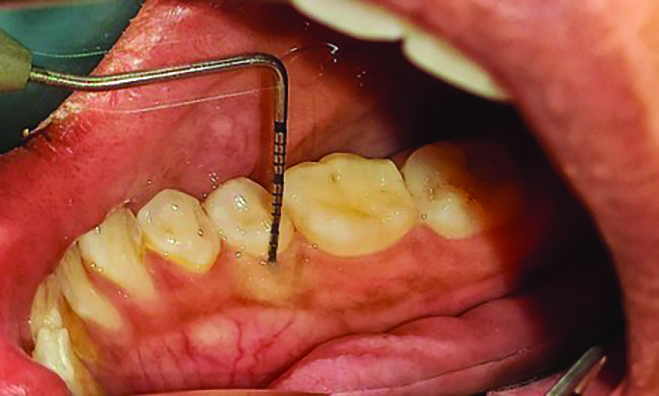

The MGJ was delineated by the visual method and the roll method following clinical examination in dental chairs appropriately equipped. Visual assessment relies on identifying the color difference between the gingiva and alveolar mucosa. The mucosa beyond the MGJ typically appears darker red compared to the AG, helping to demarcate the MGJ. The rolling probe method entails pushing the neighboring alveolar mucosa coronally with the blunt end of a probe. It is a functional assessment method that aids in determining the boundary between gingiva and movable mucosa.10 The probing sulcus depth was subtracted from the measured KG width at the mid-lingual aspect of each tooth to determine the width of AG, and all fractional measurements were rounded off to the nearest whole number of millimeters (Figure 1 through Figure 3).

Fig 2 = sulcus depth measurement.

Figure 2

Fig 3 = determining width of keratinized gingiva.

Figure 3